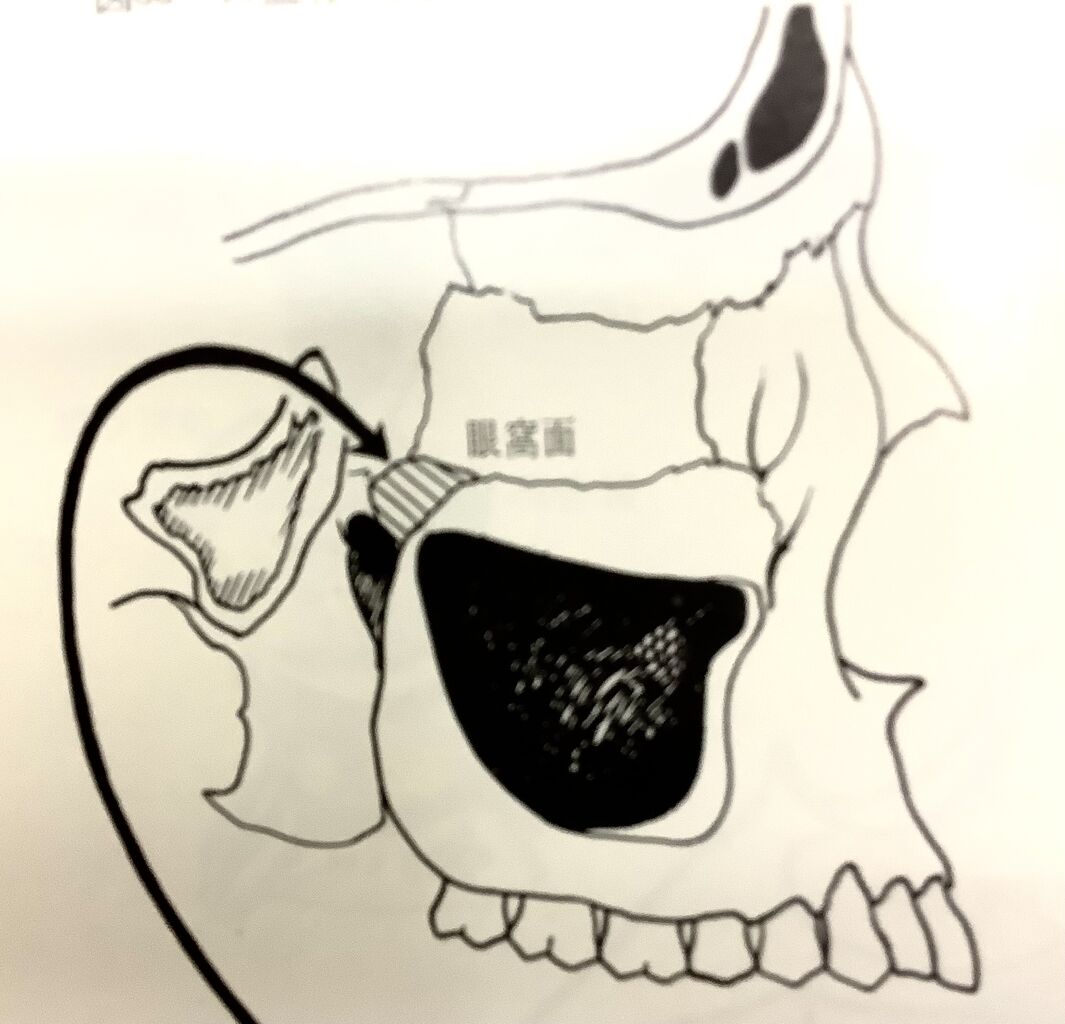

ホホの骨を取っちゃうと、こんな穴が見えてきます。

この黒い所。

上の奥歯の上にあって、空気が入っているので黒っぽく見えます。

レントゲンで白くハッキリとした境目、フチに囲まれて見えます。

で、その中にハリがあって分かれています。

大きさも様々で、歯の根っこの間や下の方まで広がっている時もあります。

奥歯を抜くと、この空洞が大きくなって下まで広がることが多いんです。

歯と近いので、お互いに影響し合う重要な場所です。